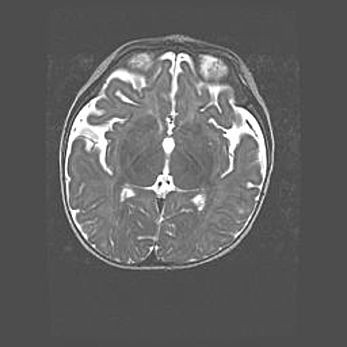

Церебральная ишемия II.

Возраст: 5 дней

Вес: 3400 г

Пол: женский

Окружность головы: 35 см

Срок гестации: 39 недель

Церебральная ишемия – это заболевание, характеризующееся недостаточностью (гипоксией) либо полным прекращением (аноксией) снабжения мозга кислородом по причине закупорки одного или нескольких сосудов. Это приводит к  что метаболическим расстройствам различной степени тяжести в тканях головного мозга, развитию коагуляционных некрозов и гибели нейронов.